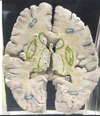

1. At what level through the cerebrum is this section taken? 2. Identify the specific structure labelled 1. 3. Identify the structure labelled 2. 4. Identify the structure labelled 5. 5. Identify the specific structure labelled 8. 6. Identify the structure labelled 10.

1. The level of interventricular foramen 2. Genu of Corpus Callosum 3. Septum Pellucidum 4. Column of Fornix 5. Spleenium of Corpus callosum 6 Crus of Fornix

56

1. Identify the specific structure labelled 3. 2. Identify one afferent fiber of this structure. 3. Identify one efferent fiber of this structure.

Caudate Nucleus Cortico striate, thalamo striate, nigro striate , Striato pallidal , Striato nigral

57

1. Identify the specific space labelled 4 2. Give its developmental origin.

Anterior horn of lateral Ventricle Central Canal of neural tube

58

1. Identify the structure labelled 6.

thalamus

59

1. Identify the structure labelled 7. 2. Give its subdivisions. 3. Give its afferent fibers. 4. Give its efferent fibers.

1. Lentiform Nucleus 2. Putamen, globus pallidus externas, globus pallidus internus 3. Corticostriatal, nigrastriatal 4. striatonigral, striatalpallidal

60

1. Identify the structure labelled 9. 2. Identify the structure labelled 11. 3. Identify the vessels lining the structure labelled 11.

1. Tail of caudate nucleus (goes to amygdala) 2. Insular cortex 3. short perforator branches from the superior division of the middle cerebral artery (MCA)

61

1. Identify the structure labelled 12 2. What type of meninges covers this structure? 3. What is the main function of this structure? 4. In which ventricular structures is this structure present? 5. In which ventricular structures is this structure absent?

1. Choroid Plexus 2. Pia Mater 3. Produces SF in ventricles of brain 4. Lateral 5. cerebral aqueduct, frontal horn of the lateral ventricle, [1] and occipital horn of the lateral ventricle

62

1. Identify the specific structure labelled 13. 2. What fibers can be found in this structure?

1. Posterior Limb of Internal Capsule 2. Corticospinal Fibres

63

1. Identify the specific structure labelled 14. 2. What fibers can be found in this structure?

1. Anterior Limb of internal capsule 2. Frontopontine, thalamocortical